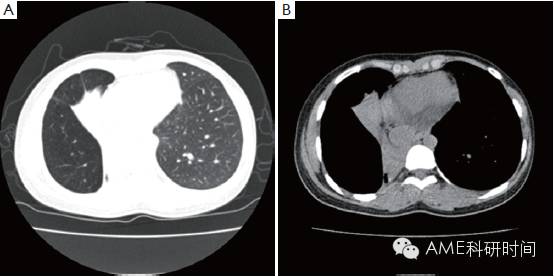

女,18岁,因为活动后因心悸伴气短半年余,间伴有干咳,而在2013年5月18日入院。入院后做胸部CT提示右中肺不张(图1),纤支镜检查示提示右主支气管开口肿物,病理活检结果提示“支气管粘液表皮样癌”(图2A)。做好手术前准备,2013年6月5日,在手术室全麻下行VATS右中下肺支气管袖状肺叶切除,淋巴结摘除术,术中见右中下肺阻塞性肺不张,右上肺过度胀气膨胀,气管旁隆突下淋巴结有肿大,予行右中下肺支气管袖状肺叶切除,淋巴结摘除(视频1)。气管断端送冰冻病理检查,结果示“未见癌残留”。术后病理结果示“支气管粘液表皮样癌”(图2B),第2,4,7,8,11,12组淋巴结未见转移癌。手术后给予抗炎及对症治疗,恢复良好,术后第10天出院。手术后1个月,复查胸部CT扫描,显示右上叶支气管通畅(图3)。

(图 1 胸部CT提示右中肺不张。(A)肺窗;(B)纵隔窗。)